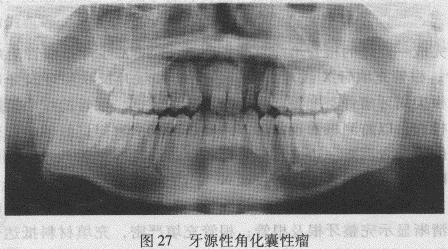

4.牙源性角化囊性瘤是发生于颌骨良性、单囊或多囊牙源性良性肿瘤,具有侵袭性和浸润性生长的特点。在临床上具有一定的复发倾向;约10%的患者具有多发性。下颌较上颌多见,肿瘤好发于磨牙、升支区,其次为上颌窦区。X线表现以单囊多见,常沿颌骨的长轴发展,颌骨膨胀多向舌侧亦可穿破舌侧骨板。牙根吸收少见,多呈斜面状。肿瘤内可含牙或不含牙。多囊仅占20%~30%,多囊者囊腔大小相近;对于多发性牙源性角化囊性瘤应选择曲面体层摄影为佳(图27)。

4.牙源性角化囊性瘤是发生于颌骨良性、单囊或多囊牙源性良性肿瘤,具有侵袭性和浸润性生长的特点。在临床上具有一定的复发倾向;约10%的患者具有多发性。下颌较上颌多见,肿瘤好发于磨牙、升支区,其次为上颌窦区。X线表现以单囊多见,常沿颌骨的长轴发展,颌骨膨胀多向舌侧亦可穿破舌侧骨板。牙根吸收少见,多呈斜面状。肿瘤内可含牙或不含牙。多囊仅占20%~30%,多囊者囊腔大小相近;对于多发性牙源性角化囊性瘤应选择曲面体层摄影为佳。